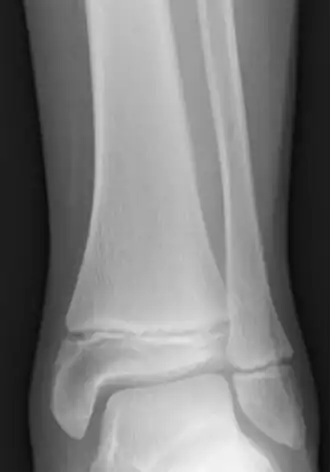

![]() Radiografia da parte inferior da perna de uma criança de 12 anos, mostrando placa epifisária em crescimento na tíbia e na fíbula. | |